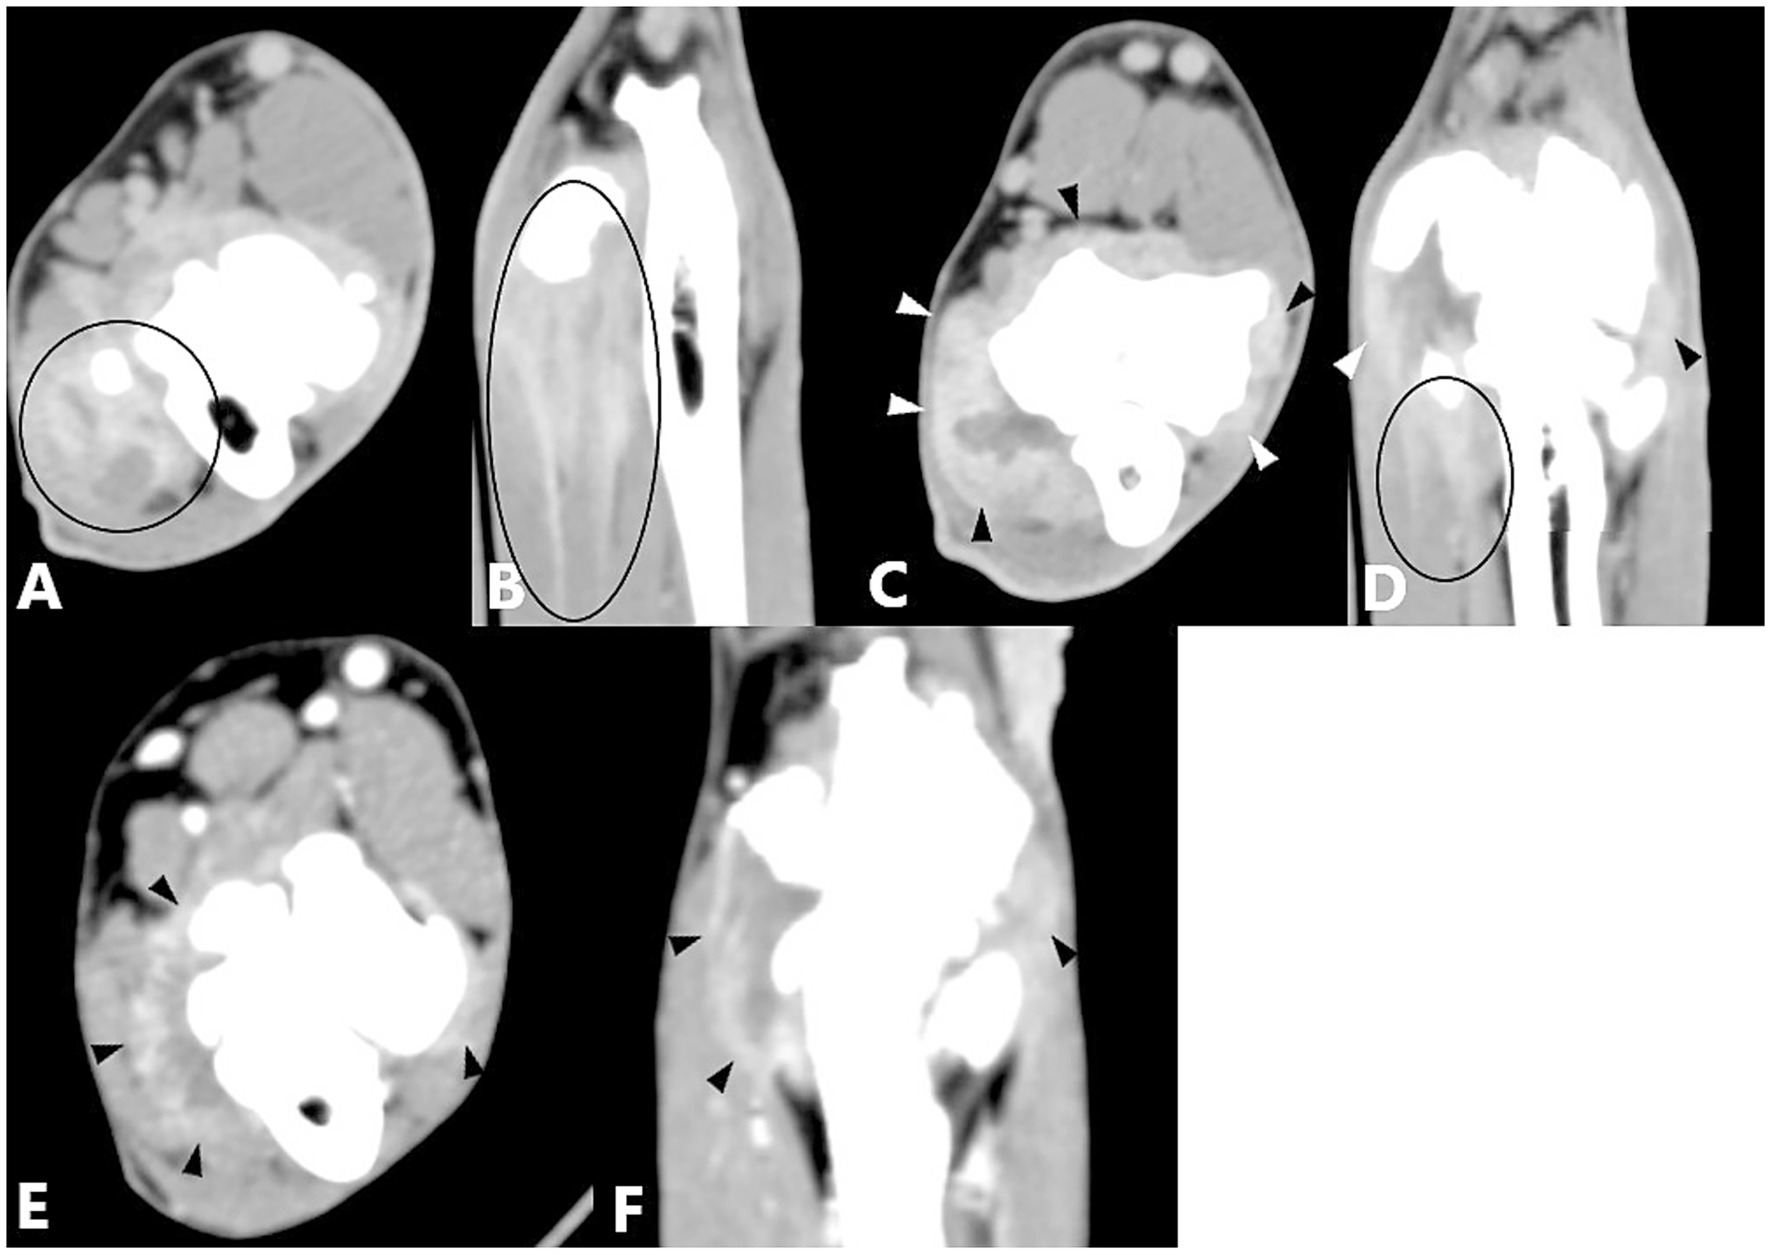

CT images obtained after contrast administration were examined in the soft-tissue window to identify enhancement of the joint capsule, one or more flexor muscles, or their origin tendons. The degree of enhancement was not considered in the analysis. Enhancement of the joint capsule was defined as a hyperattenuated periarticular area (Figure 1). Enhancement of the flexor muscles was defined as a hyperattenuated area within the flexor muscles or their origin tendons, or as a hypoattenuated center surrounded by a hyperattenuated rim (Figure 2). Joint capsule and flexor muscle enhancement could occur simultaneously in a single joint. Because of the high sensitivity of CT imaging in detecting flexor enthesopathy, elbow joints with flexor muscle enhancement were considered to have flexor enthesopathy (12). The control group, used for comparison with diseased elbow joints, comprised the elbow joints of included dogs that showed no evidence of periarticular osteophytes on radiography or CT in the bone window, no lameness (contralateral joints), and no contrast enhancement.

Figure 1. Computed tomography slices after contrast agent administration showing enhancement of the joint capsule. (A) Transverse CT slice of a right elbow joint with increased joint fluid and enhancement of the joint capsule (black and white arrowheads). (B) Dorsal reconstruction of the same elbow joint shown in (A) demonstrating increased joint fluid and enhancement of the joint capsule (black arrowheads).